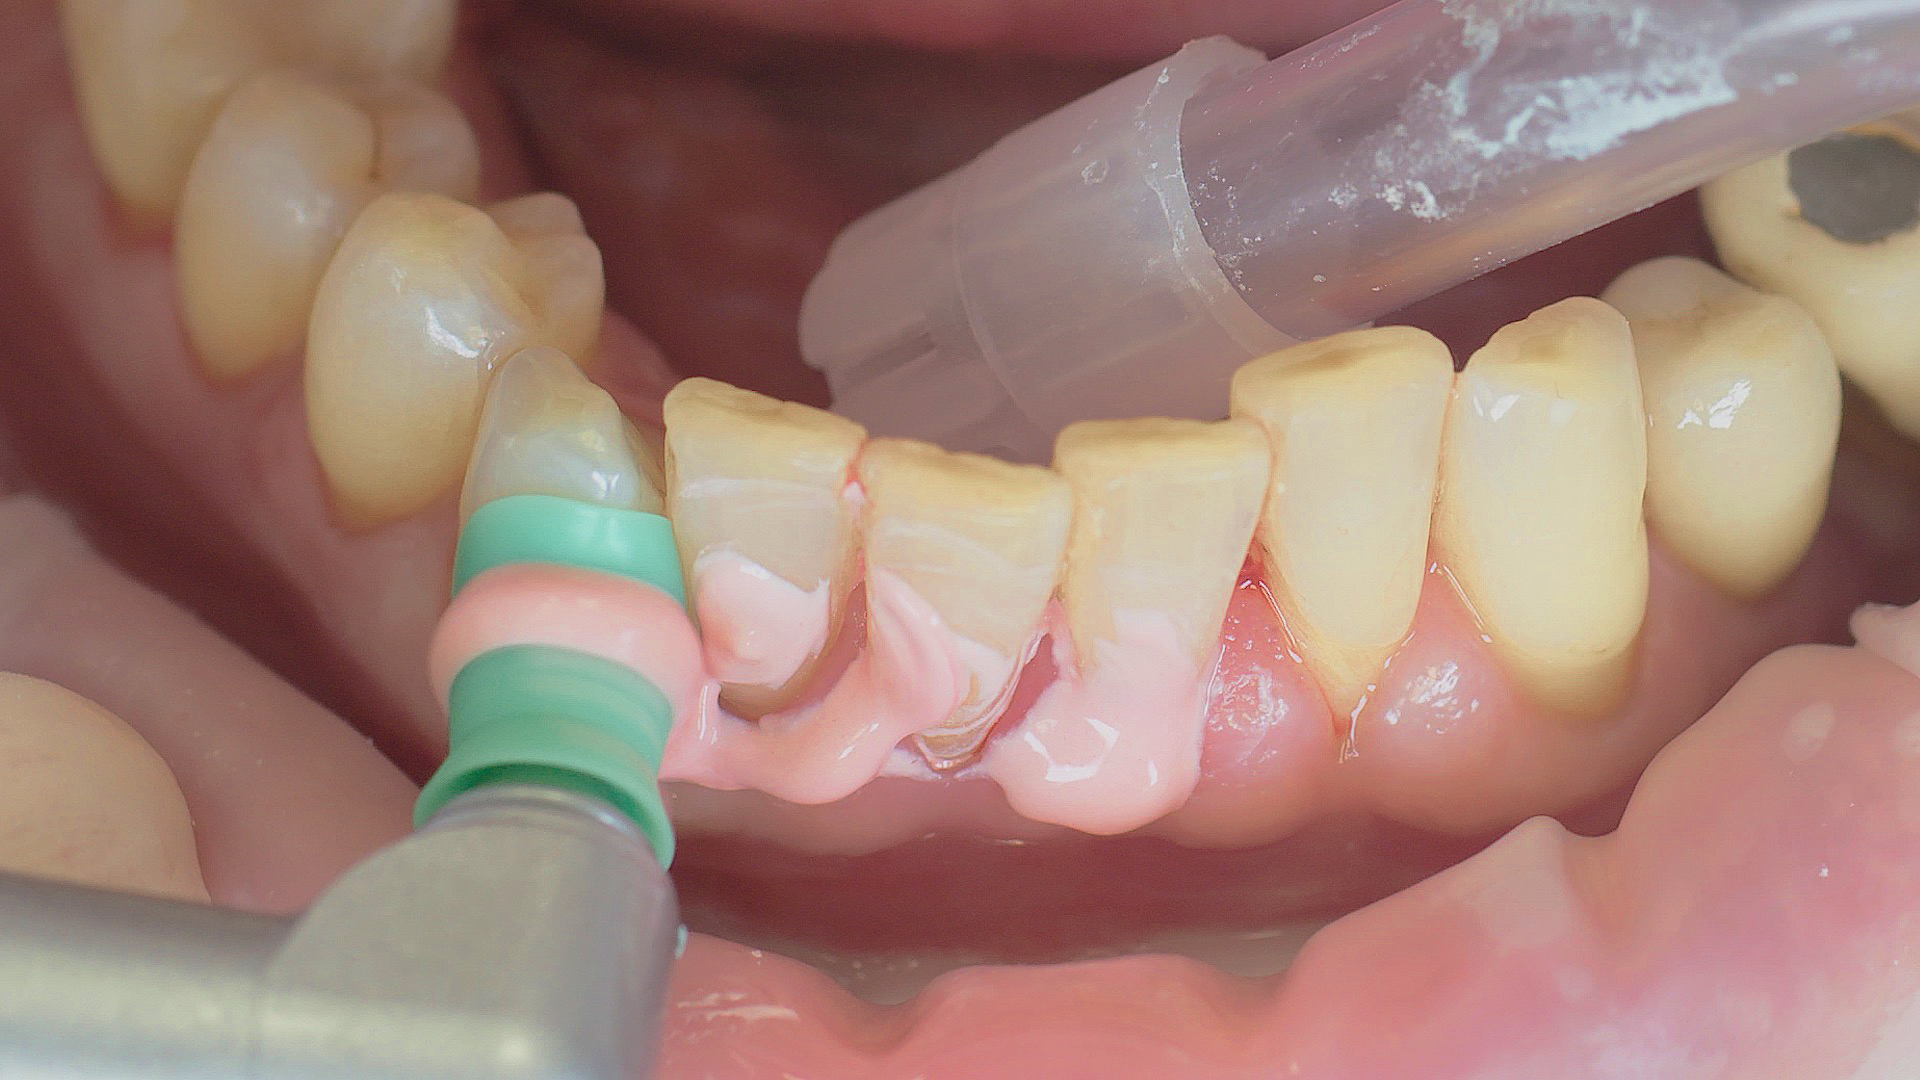

Healthy peri-implant tissue does not show any signs of redness, swelling or bleeding, neither does it secrete pus when probed.[5] Based on the consensus document, Prof. Giovanni Salvi explained the importance of regu- lar probing — preferably with a flexible probe, as implant components often tend to obstruct the procedure.[5] In the case of mucositis or initial peri-implantitis already being present, the non-surgical removal of hard deposits and biofilm should be attempted first. For this purpose, ultra- sonic power and special instruments designed to protect the implant should be employed (Fig. 3; piezo scaler Tigon+ with 1I, W&H). In case of no remission, the recall frequency needs to be increased. However, specific recommendations, applicable to individual cases, are not yet available in this context.[15]